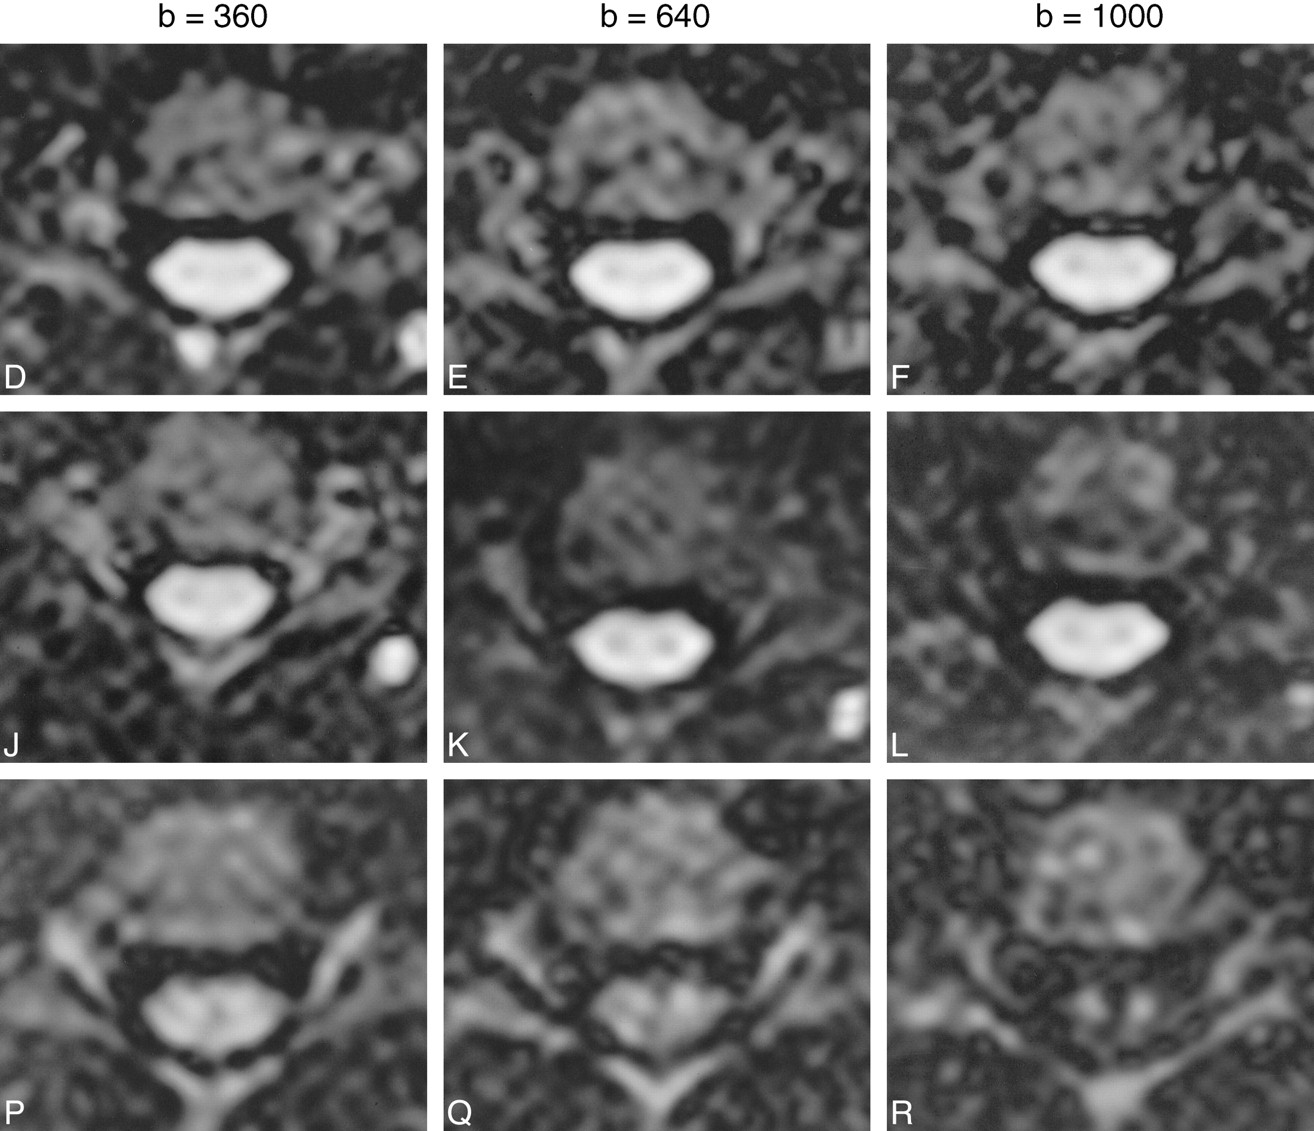

Axial diffusion-weighted images (2 R-R/106/4 [TR/TE/excitations]) showing the appearance of the cervical spinal cord with the diffusion-probing gradients in the three cardinal axes, with increasing b values from left to right. R-L, A-P, and C-C indicate the direction of the diffusion gradients. The R-L and A-P directions are perpendicular to the white matter tracts. The C-C direction is parallel to → the white matter tracts. Note the relatively greater signal attenuation with the diffusion gradients in the C-C direction, reflecting the underlying tissue anisotropy. Note also the reversal of the relative signal intensity of gray and white matter at the higher b values (640, 1000) in the C-C direction, due to the higher ADC of white matter along this axis